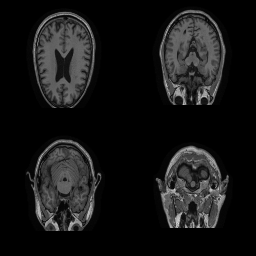

| Original | Renderings after de-identification | Original | MRI slices after de-identification | ||||||

|

![]() |

||||

| CP-GAN | FACE MASK | DEFACE | QUICKSHEAR | CP-GAN | FACE MASK | DEFACE | QUICKSHEAR | ||

Benchmark De-Identification Methods. We compare our result with three publicly available and widely-established methods for de-identification of MRI head scans, depicted in Figure 3. All methods have in common that they (1) are not deep-learning-driven, (2) require no additional training and (3), are used on a day-to-day basis in neuroscience and clinical research. All procedures were applied with default settings on images of resolution . The methods include QUICKSHEAR [Schimke et al.(2011)Schimke, Kuehler, and Hale], FACE MASK [Milchenko and Marcus(2013)], and DEFACE [Bischoff-Grethe et al.(2007)Bischoff-Grethe, Ozyurt, Busa, Quinn, Fennema-Notestine, Clark, Morris, Bondi, Jernigan, Dale, Brown, and Fischl]. Descriptions of the methods are provided in the Appendix. We also include MRI WATERSHED [Ségonne et al.(2004)Ségonne, Dale, Busa, Glessner, Salat, Hahn, and Fischl], a skull-stripping method that removes everything except the brain.